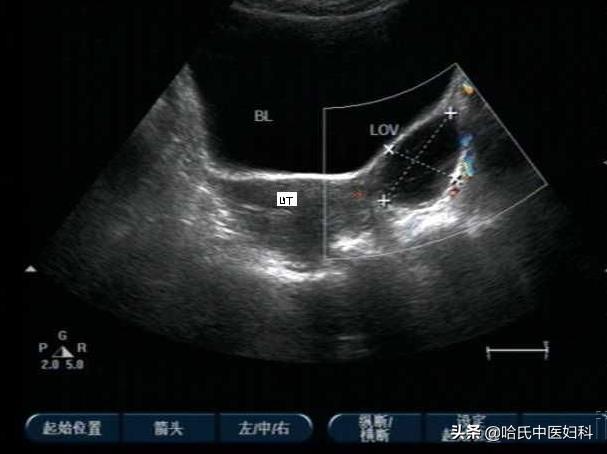

患者王某,女,32岁,平素月经量少,4-5日净,有少许血块,色黑,右下腹隐痛,因备孕2020年7月1日在外院做孕前检查,B超示:宫内膜回声不均、子宫肌壁回声不均、右侧卵巢探及8.4cm*5.4cm*6.0cm囊性包块,包膜完整囊液透声好。该院医生建议手术治疗,因本人考虑尚未生育且术后仍会复发故不同意。

二诊丨 服药两周后,小腹疼痛消失,并于2020年7月18日到医院复查B超:右侧卵巢探及6.7cm*4.5cm*5.6cm囊性包块,包膜完整囊液透声好,张力稍差。舌略红,苔瘀斑减退,脉沉。守上方加*党**参,炒麦芽;

三诊丨 2020年9月27日B超检查示:右侧卵巢探及大小约4.4cm*2.9cm的囊性包块;包块缩小一半且宫内膜回声及子宫肌壁回声均匀。虽B超提示右侧卵巢包块考虑为生理性,舌质淡苔薄白,脉沉细。守上方加减化裁,进服一月;

四诊丨 2020年10月23日B超示:囊性包块缩小至3.1*2.6cm,边界清,其内可见絮状回声。守上方进服一月;

五诊丨 2020年11月20日B超显示:子宫附件无异常。